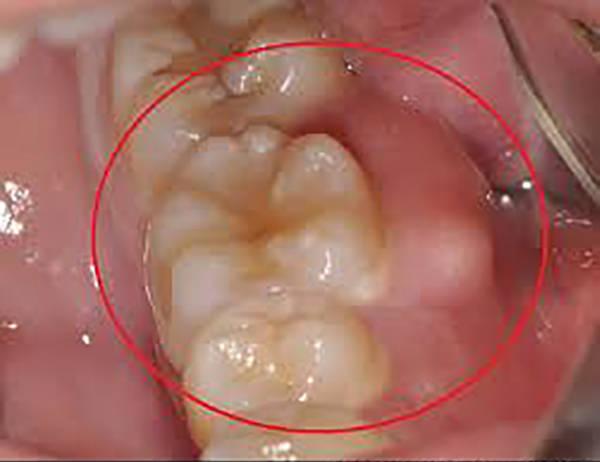

龋病

龋病是由于细菌的作用造成牙体硬组织脱矿和有机物分解,表现为牙体硬组织的变色、脱钙软化和龋洞形成,病变进一步发展可伴随牙髓充血、牙髓炎、牙髓坏死、根尖周炎、根尖周脓肿等。龋坏严重者,可造成牙冠部分或全部破坏,形成残冠、残根。